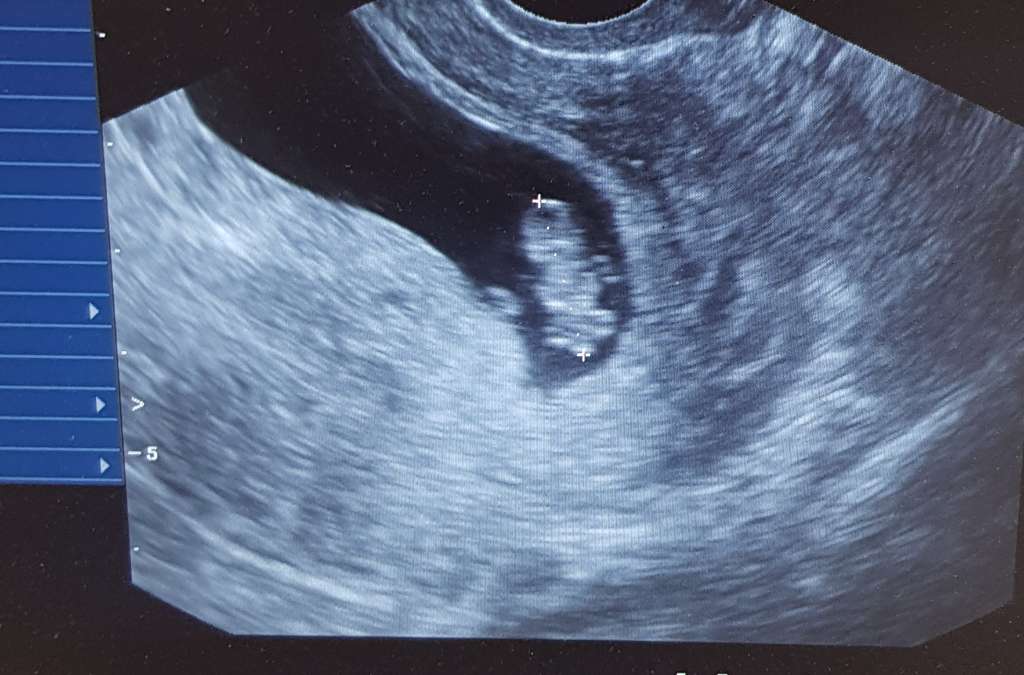

Cześć dziewczyny. Witam się z Wami. Jestem w trzeciej ciąży. Na początku było dużo obaw, nadal są, ale im ciąża wyższa tym ma się więcej nadziei, że będzie wszystko ok. Jestem mamą dwóch chłopców, teraz trzecia ciąża i zastanawiam się czy w brzuszku mieszka trzeci chłopczyk, czy może dziewczynka. Dzisiaj porównywałam sobie układ dzieci w brzuszku i zastanawiam się czy on może mieć wpływ na płeć. Zobaczcie same. Trzeci bobo też ma taki sam uklad, czyli główka z lewej strony, pupka z prawej. Mamy które mają kolejną ciążę może podpowiecie czy u Was się to sprawdziło. Czekam na moją upragnioną perełkę, chociaż to dopiero 10 tydzień to już się jej nie mogę doczekać. Pozdrawiam Was mamusie 😊

Załączniki

• 1c2304bf-1d0b-44a3-ac40-d889a97e3c9f.jpg

1c2304bf-1d0b-44a3-ac40-d889a97e3c9f.jpg

69 KB · Wyświetleń: 92

• f6fd12f8-1ad6-4337-8200-7c1bd2b0afa6.jpg

f6fd12f8-1ad6-4337-8200-7c1bd2b0afa6.jpg

89,4 KB · Wyświetleń: 99